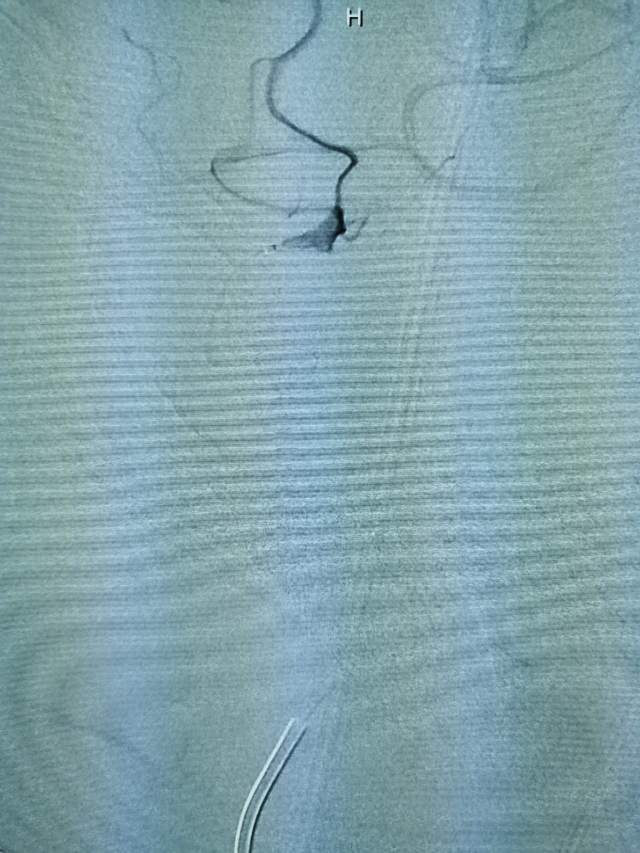

儿子很是着急,多方打听后,转来我院。入院后的评估发现左侧颈内动脉已经闭塞2个月了,左侧的大脑半球“红彤彤”的一大片,就像燃烧的“火焰山”。处于严重的缺血状态,人怎么可能有活力呢~

一个月后根据复查情况酌情给予二期支架植入